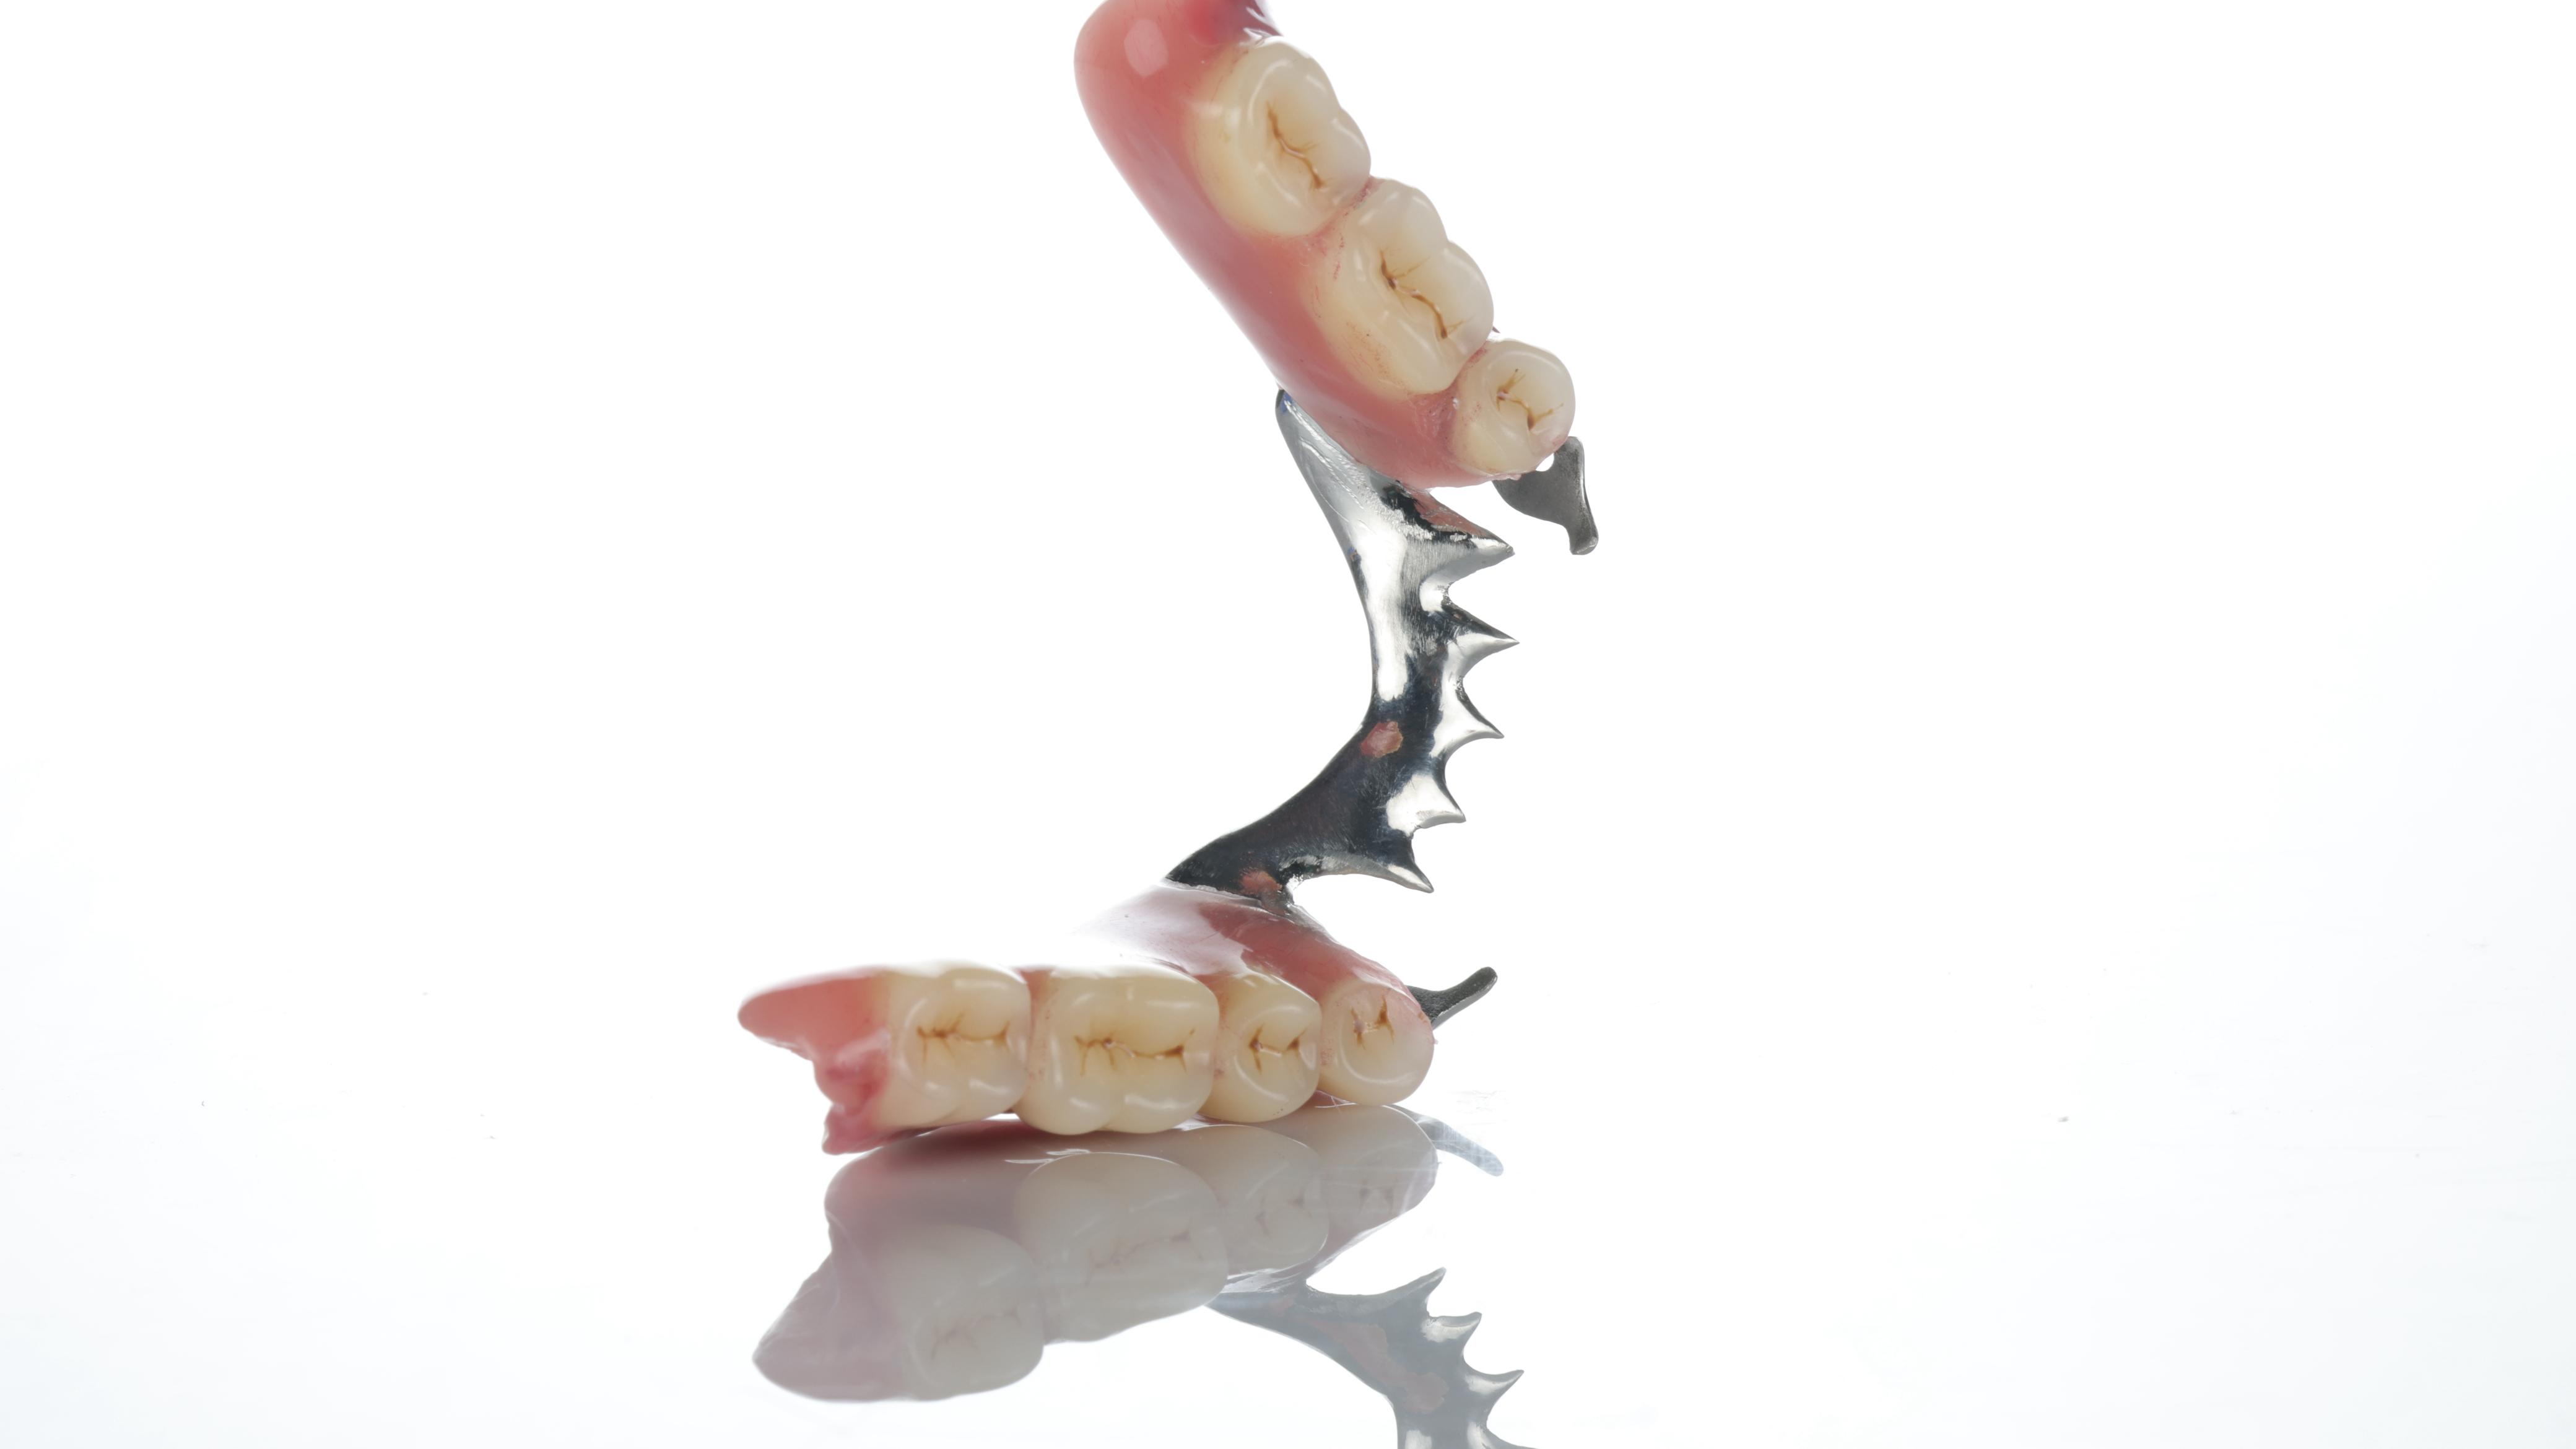

• Equipment